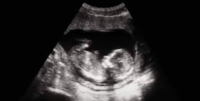

El personal médico del Hospital Materno Infantil San Lorenzo de Los Mina mantiene sus esfuerzos por salvar la vida de una menor de 12 años que permanece ingresada en la Unidad de Cuidados Intensivos, tras haber perdido un embarazo de 37 semanas.